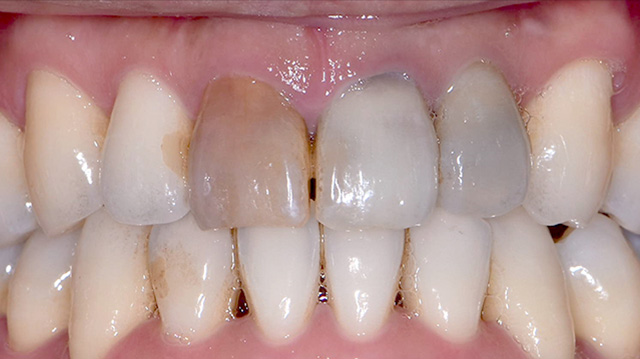

| 年代・性別 | 30代 男性 |

|---|---|

| 主訴 | 前歯の色が気になる |

| 治療期間 | 約1年 |

| 費用 |

仮歯 5,500円 × 2 ジルコニアクラウン 176,000円 × 3 インプラント 300,000円 インプラント仮歯 22,000円 サージカルガイド 70,000円 |